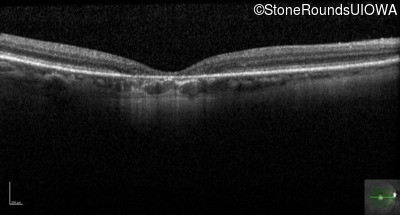

This 59 year old woman first noticed a reduction in her visual acuity and photophobia in her late teens.

| AD Cone and Cone Rod Dystrophy | GUCA1A | Glu155Gly GAG>GGG | AD |